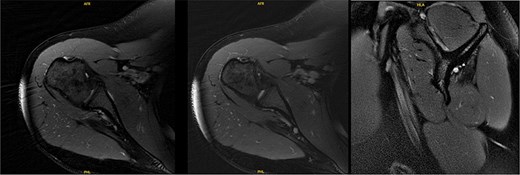

Ten years after initial presentation, the patient returned with increased right shoulder pain after overhead injury at the gym. Her exam included a positive O’Brien’s test, and external rotation weakness. Interval EMG was normal; MRI demonstrated mild supraspinatus tendinosis, and infraspinatus atrophy with unchanged fatty infiltration (Fig. 6). The patient’s pain was hypothesized to be due to infraspinatus atrophy and overuse of other rotator cuff musculature. She elected to manage her symptoms with self-directed therapy.

MRI at final follow-up demonstrated mild supraspinatus tendinosis, and infraspinatus atrophy with continued significant fatty infiltration, unchanged from prior imaging.